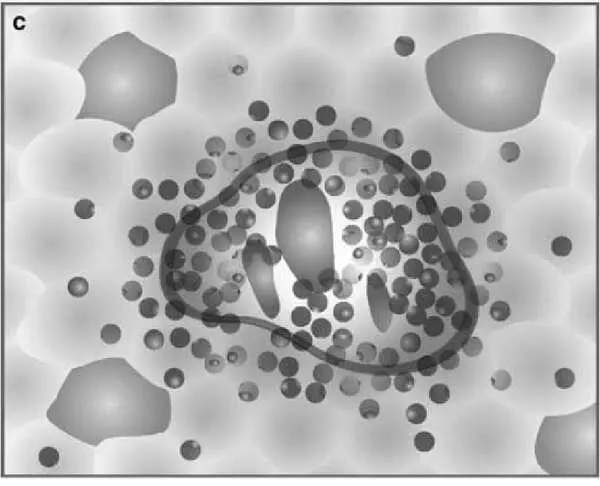

Разработчики ставили цель упростить шкалу. Оригинальность подхода заключается в том, что шкала представлена в виде 4 диаграмм, оценивающих некротические и воспалительные изменения в биоптате печени, и 4 диаграмм, оценивающих стадию фиброза .

Рисунок 5 – Схемы некротических и воспалительных изменений в печени (по Batts KP, Ludwig J.)

На рисунке представлена последовательная схема некротических и воспалительных изменений в печени при хроническом гепатите (по Batts–Ludwig). Воспалительная инфильтрация портальных трактов является обязательным компонентом поражения печени при гепатите и оценивается во всех системах. В оценочной шкале Баттс–Людвига выраженность гистологической активности гепатита градируется от 1 до 3 (a, b, c). На рисунке d представлена схема сливных некрозов в виде мостовидных некрозов, которые свидетельствуют о выраженной степени активности гепатита и соответствуют 4 стадии активности по системе Баттс–Людвига (Batts KP, Ludwig J. Chronic hepatitis. An update on terminology and reporting. Am J Surg Pathol 1995;19:1409–1417.15).